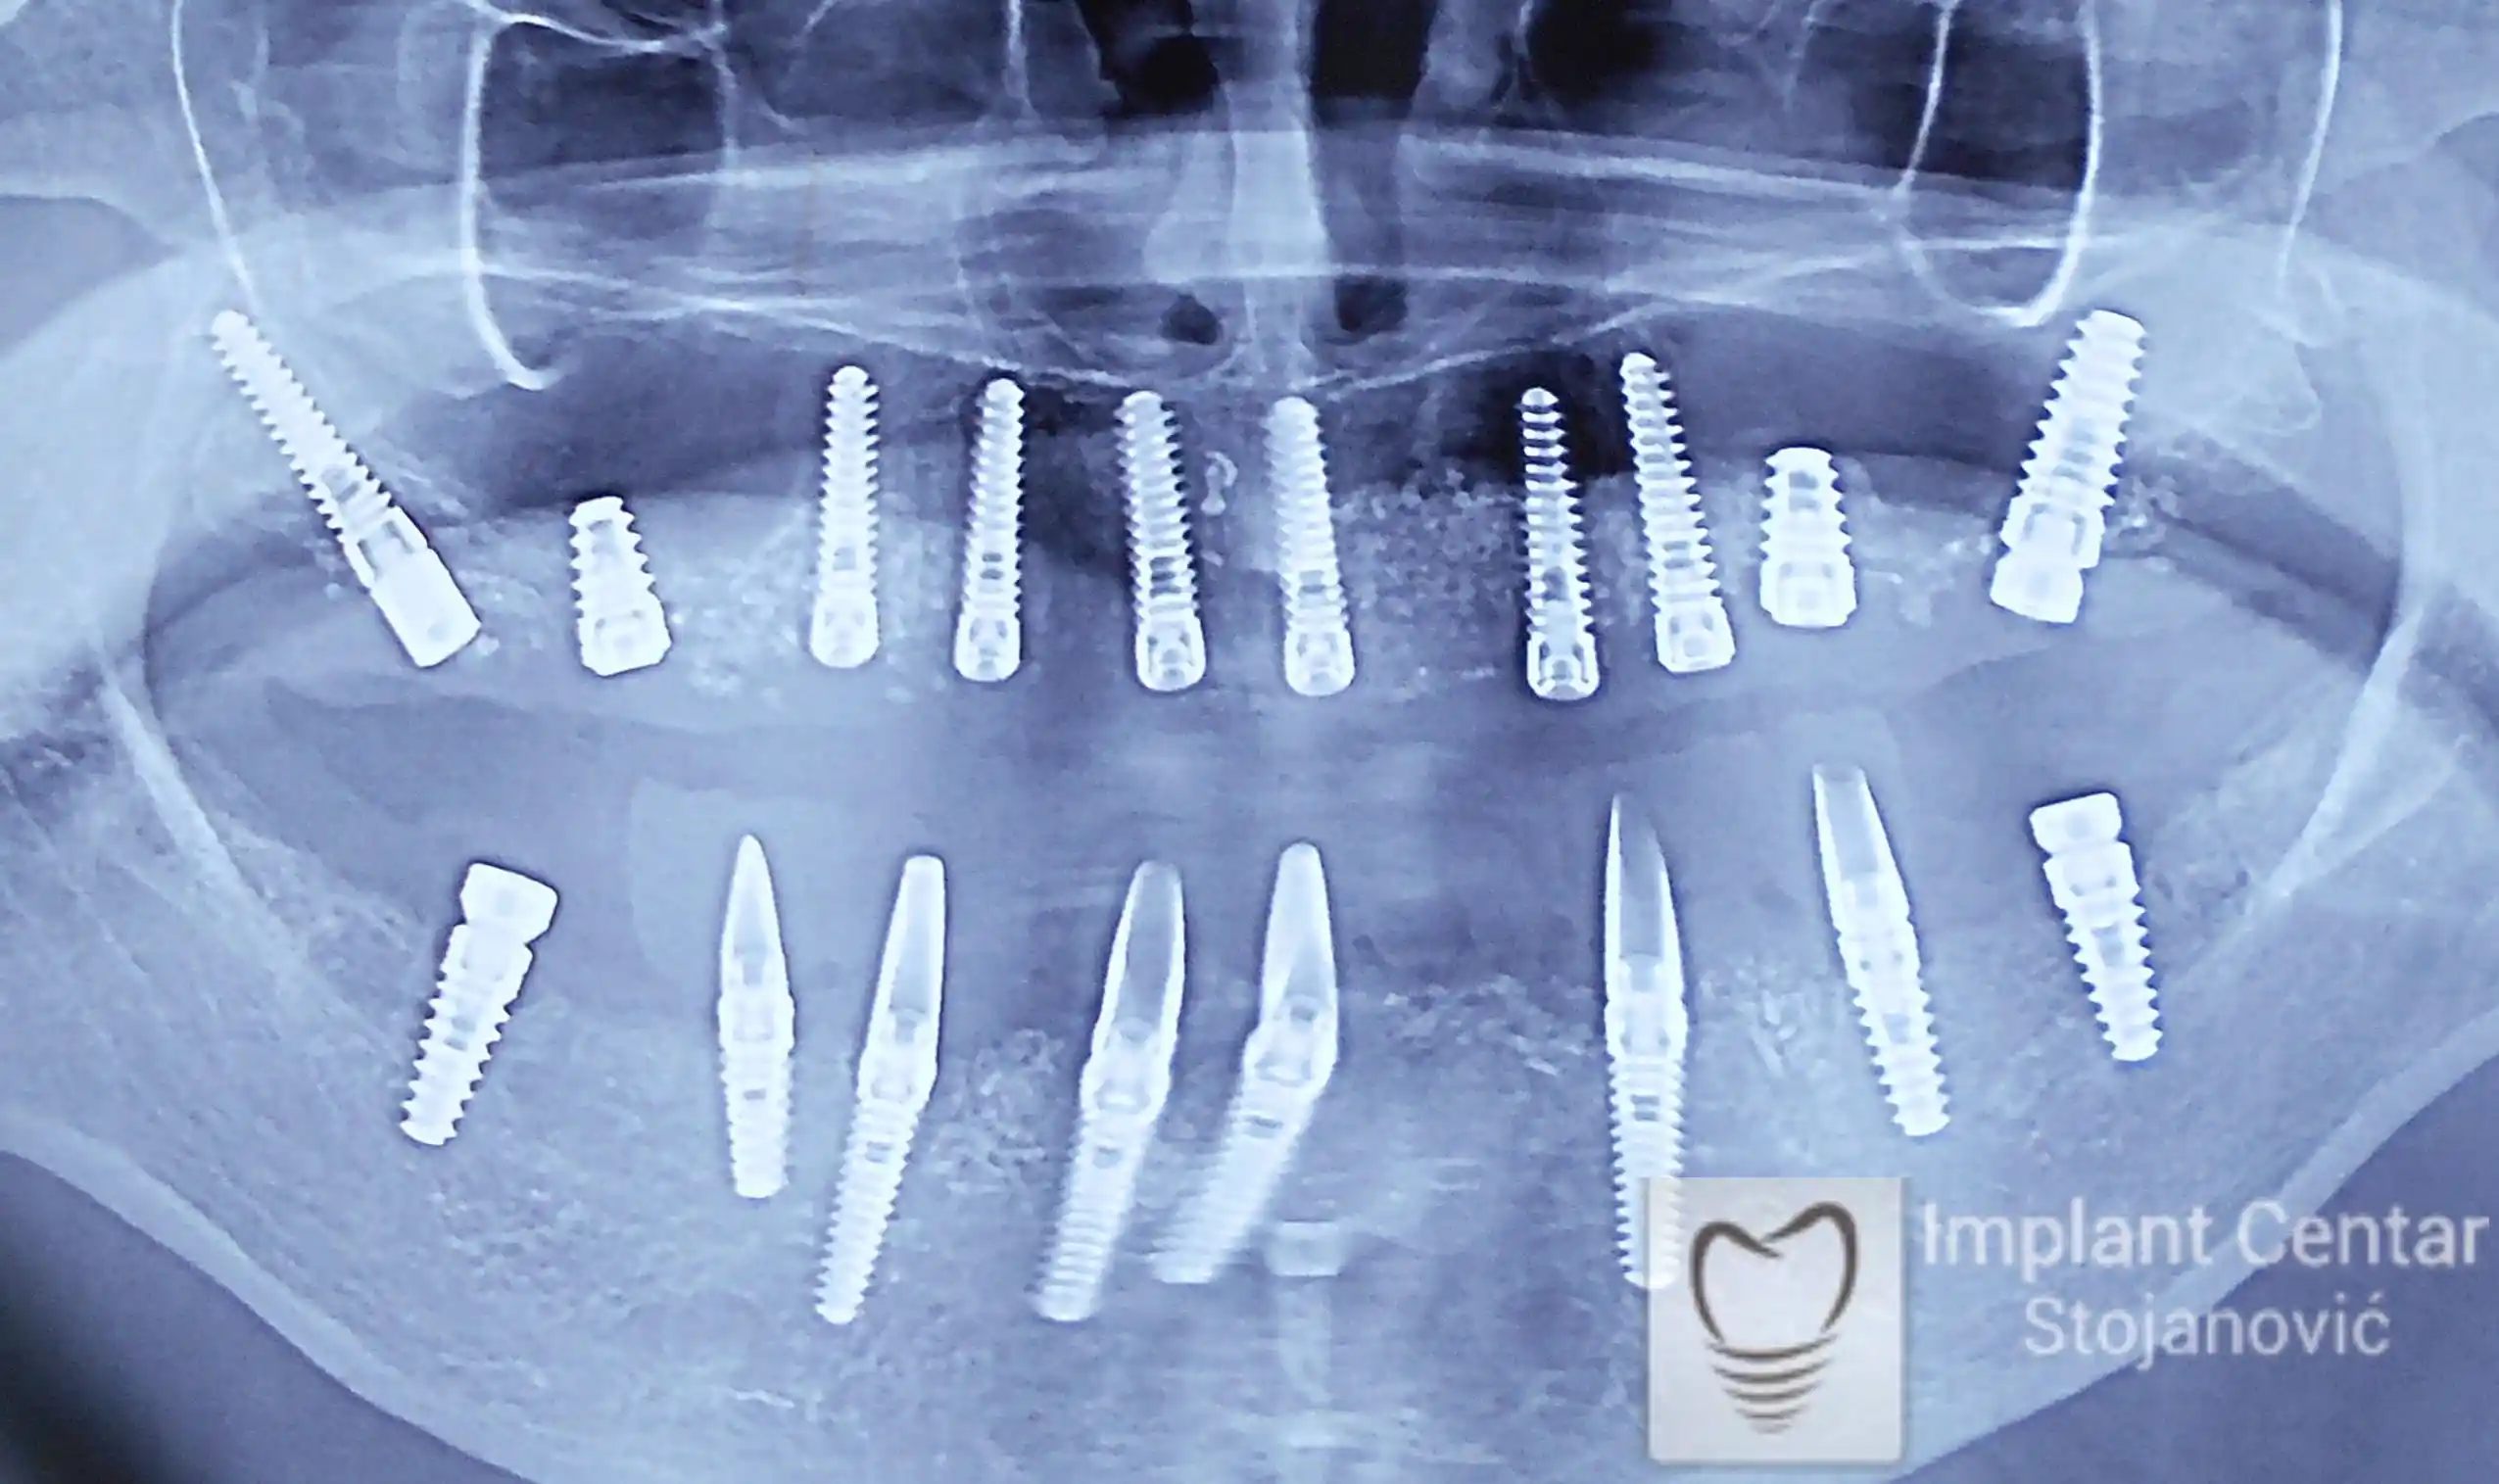

Nakon vađenja zuba, ugrađeni su implantati. Na slici 3 prikazan je ortopan snimak sa ugrđenim implantatima. Tokom perioda osteointegracije, pacijent je bio zbrinut fiksnim privremenim krunicama na implantatima, koje su izrađene samo dva dana nakon hirurške intervencije.